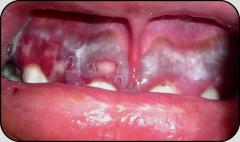

Masculino de24 años.

Masculino de 23 años

Masculino de 34 años.